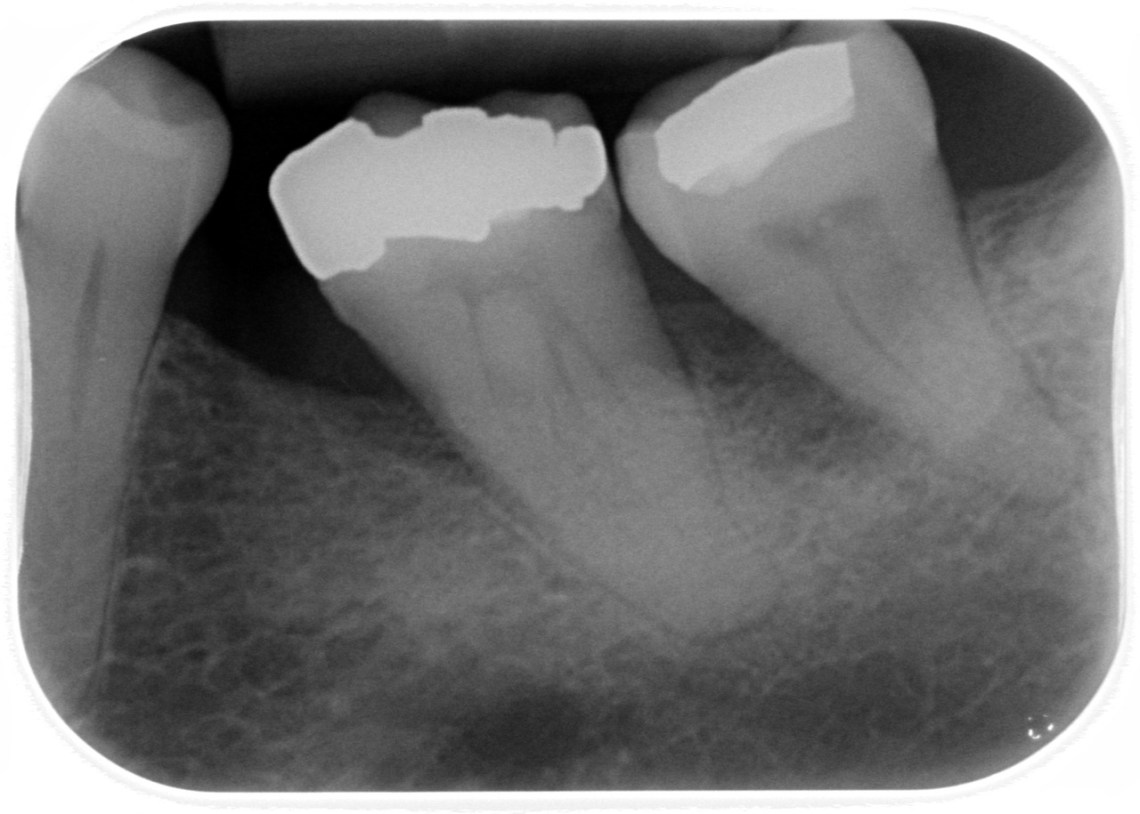

Mon 21 Aug 17: tooth problem yesterday and the first time I’ve volunteered for an extraction. My dentist is the excellent Max at Hurst Park Dental and I’m trusting that this will be as painless as the two other extractions he’s done. Looks like a big one …